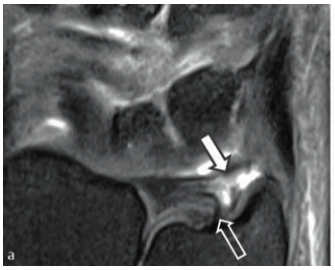

특히 2024년 Schmitt 등의

연구에서 강조한

'중심와 층(foveal lamina)'을

주목해야 합니다.

이 부위는 TFCC의 뿌리에 해당하고

척골 뼈의 깊숙한 곳(fovea)에

붙어 있다고 말씀드렸죠.

0.2mm 단위로 영상을 만들어주는

고해상도 인플레인 3.0T MRI 검사가

필수적인 것이죠.